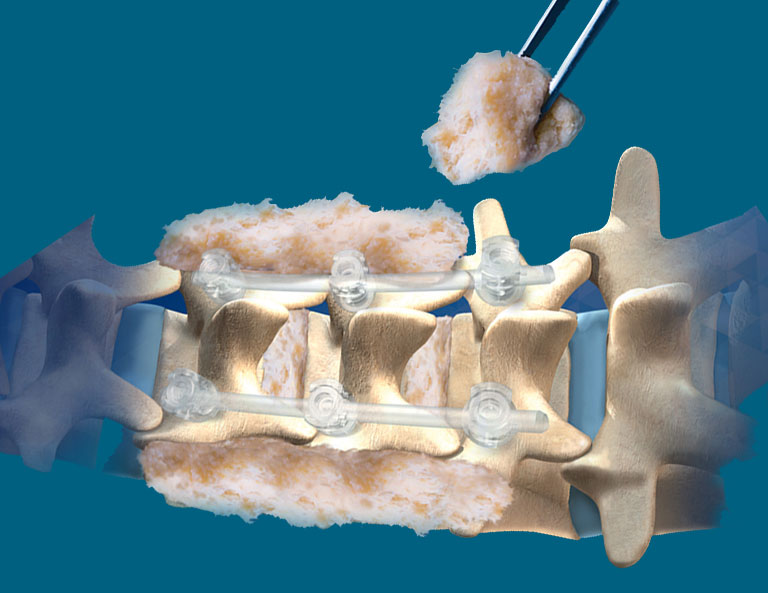

GalMed proudly offers a premium selection of biologic allografts and xenografts sourced directly from renowned tissue banks in the USA and Europe. These high-quality graft materials are essential tools for surgeons performing orthopedic repairs, dental procedures, and burn treatments. Designed to support natural healing and effective tissue regeneration, our biologic solutions provide healthcare professionals with the utmost safety and efficacy. By choosing GalMed, you’re investing in products trusted worldwide for their rigorously tested standards and transformative results in patient recovery and care.

GalMed provides an extensive range of top-tier medical supplies and equipment tailored to the diverse needs of healthcare providers. Our offerings span various specialties, including orthopedics, dental, burn care, and aesthetics.